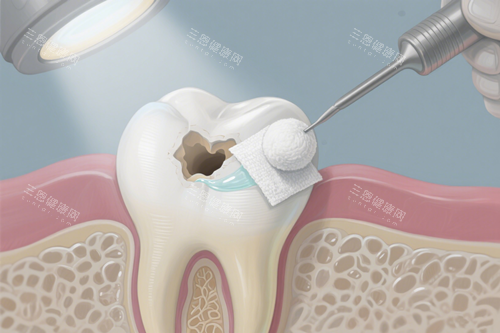

接下来就是补牙了,张医生先给我做了局部麻醉,他说“可能会有点胀胀的感觉,别害怕”。麻醉起效后,他用正规的工具清理蛀坏的部分,过程中会时不时问我“疼不疼?有不舒服就举手”。我本来还担心会有刺耳的声音,结果发现他们用的器械噪音特别小,而且护士一直在旁边帮我吸口水,递工具,服务特别周到。

选好材料后,张医生就开始填充了。他特别细致,填充完还会用工具一点点塑形,打磨,直到和我的牙齿形状完全贴合。补完后,他让我咬合几下,问我“有没有高低不平的感觉?”,调整到合适的高度后,又用光照固化,整个过程大概也就二十多分钟。